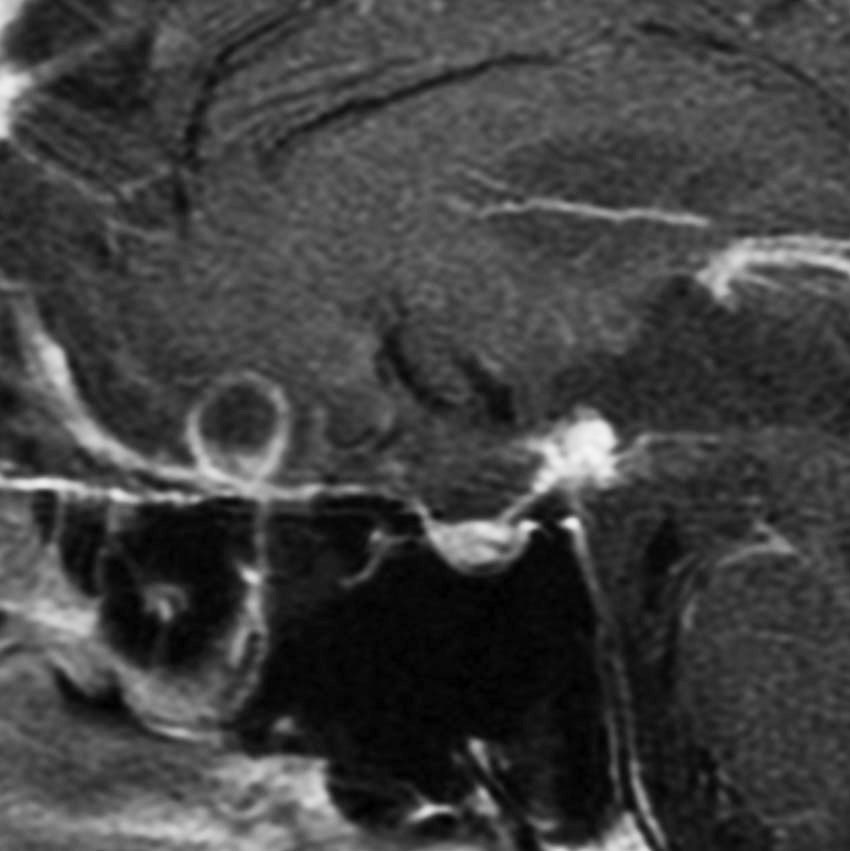

8歳で両側の視力低下が生じました。眼科では精神的なものと診断されて,4ヶ月くらいで右視力 0.4(耳側半盲),左指数弁となりました。のう胞性頭蓋咽頭腫で大きな骨化を伴うもので1月くらいの間に全盲になるかもと判断しました(失明寸前です)。

矢印の先に見えるように下垂体は正常の形態です。この画像から灰白隆起の左後方,乳頭体の前方が腫瘍発生母地ということがわかります。尿崩症もなく下垂体機能は正常です。経鼻的な内視鏡手術で腫瘍の大部分を摘出すれば下垂体機能は廃絶します。

とにかく失明を避けるために急いで経蝶形骨洞手術(transsphenoidal-transtuberculum sellae approach)で腫瘍のう胞の減圧をしました(緑の矢印の経路 by 函館中央病院加藤功先生)。その後に前頭開頭で腫瘍を全摘出しました(右側の画像)。尿崩症はでましたが下垂体前葉機能は正常です。

右視力 0.45,左明暗弁の視力が残りました。でももし,経鼻手術をしないでいきなり開頭すればおそらく全盲になっていた例です。